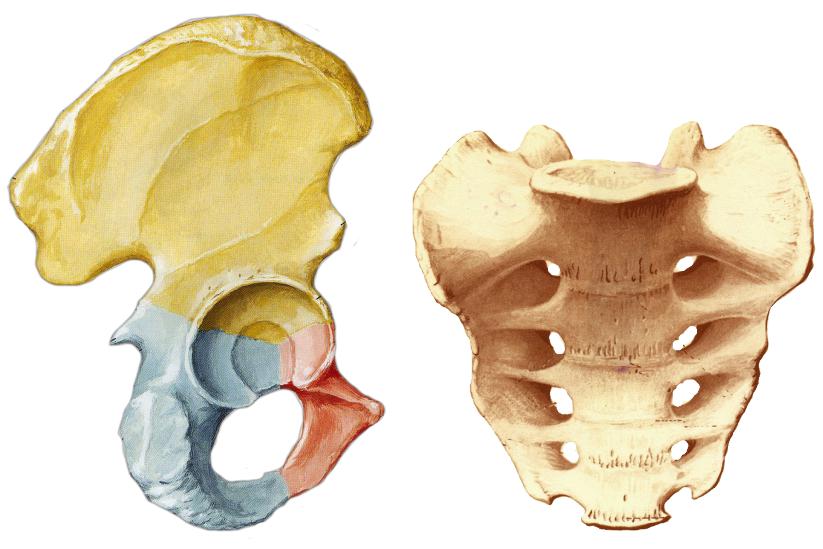

Структура и анатомия синдесмоза: научные иллюстрации